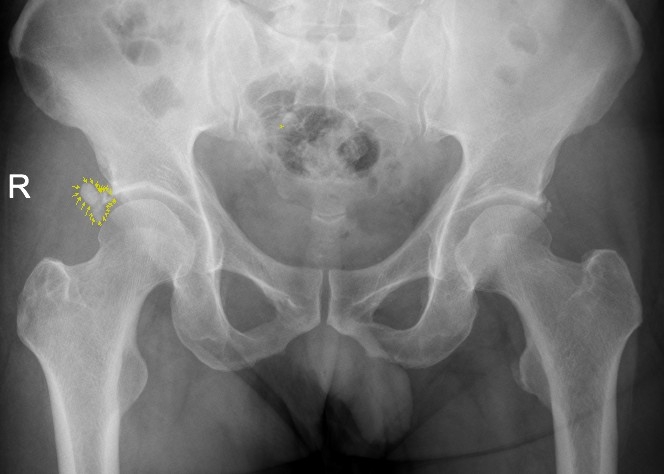

该患者为男性患者,47岁。右髋部疼痛7个多月,曾断续就医,未明确诊断,疼痛时缓时重。入院前两天,右髋部剧烈疼痛,患髋不能伸直,只能左侧卧位,谓之“坐卧不宁”,需家人搀扶下才能勉强行走。经临床经验丰富的骨三科主任、主任中医师李彬以“右髋关节盂唇病变”收入住院治疗,经X光核磁共振检查,患者右髋关节盂唇钙化。

X片显示盂唇钙化病灶